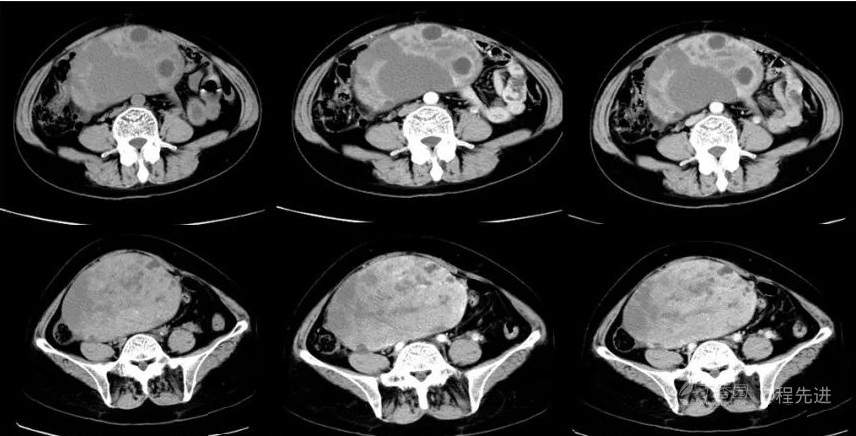

B超:中腹部混合回声肿块,性质待定